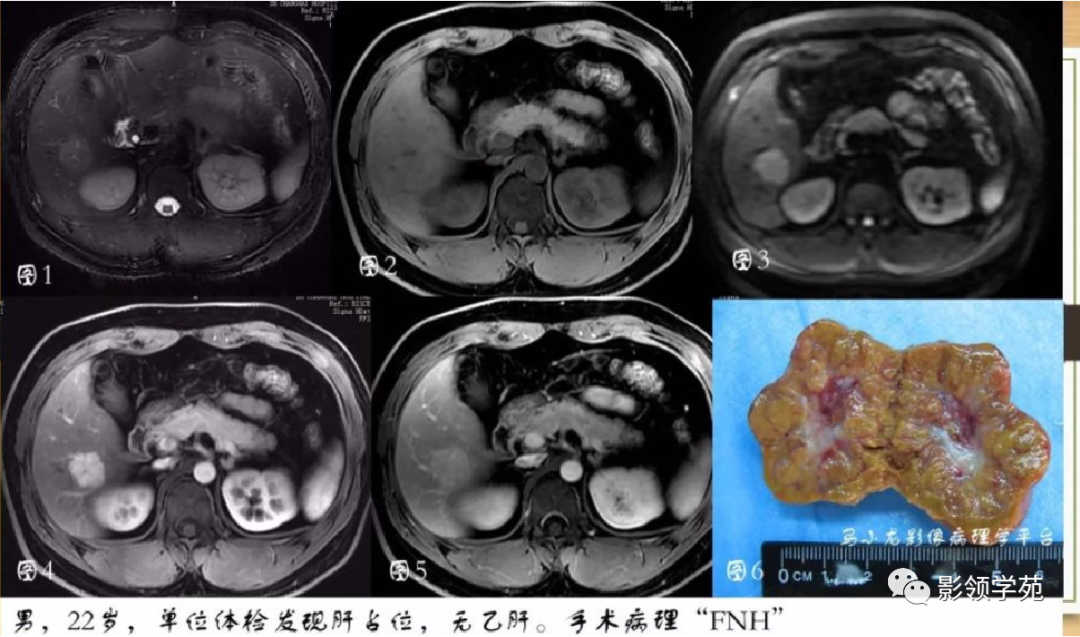

肝细胞肝癌(HCC)与胆管细胞癌(ICC)影像诊断要点